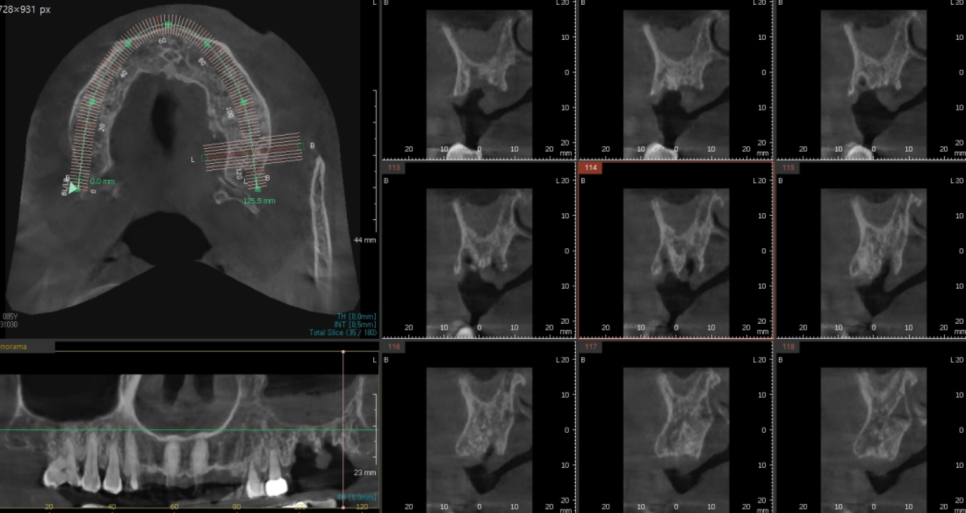

3D-CT를 통해 해부학적 구조물과 뼈를 파악하고

환자분의 구강 상태를 분석하는데

어떤 위치에 고덕동 임플란트를 심으면 좋을지

시뮬레이션을 돌려보고 또 돌려봅니다.

1-2년 쓰실것이 아니기 때문에

최적의 위치를 생각하는거죠~

임플란트 사이즈와 길이도

미리 정해두고요!